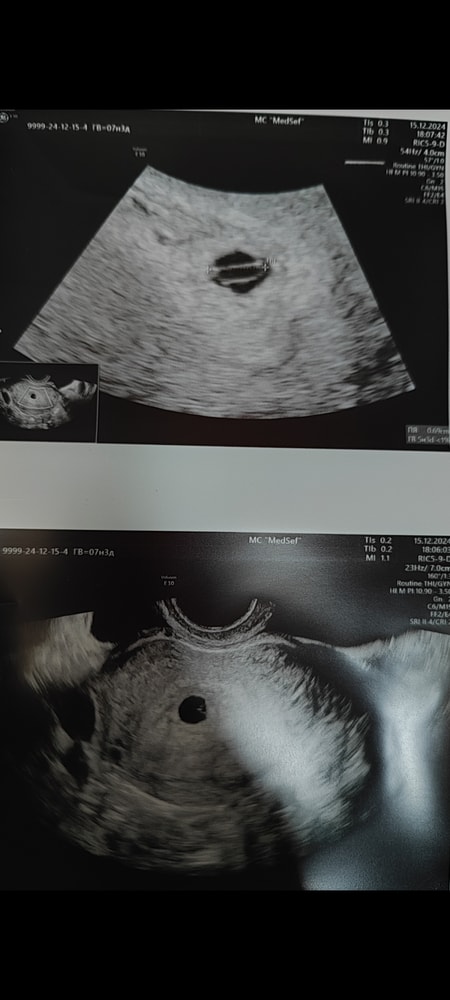

Вот покажу вам почему ждала я, у меня и при 4,8 мм и через неделю при 6,9 мм был желточный мешок. Поэтому мне говорили что есть маленькая надежда, но и то на втором УЗИ мне сказали что её уже нет, эмбрион уже должен быть. Если у вас на 6 мм ничего не было, то я думаю это было оправданное решение и не было необходимости что-то ждать.